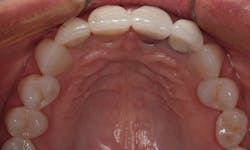

In the occlusal view in Figure 4, notice that her premolars are slightly rotated. Since both premolars were visible in her smile, it was decided to add porcelain veneers to the canines and premolars. The veneers would provide the appearance of well-aligned premolars, as well as add a lighter color. We both agreed that 10 restorations from second premolar to second premolar would be ideal.

Figure 4: Occlusal view of the patient’s initial smile